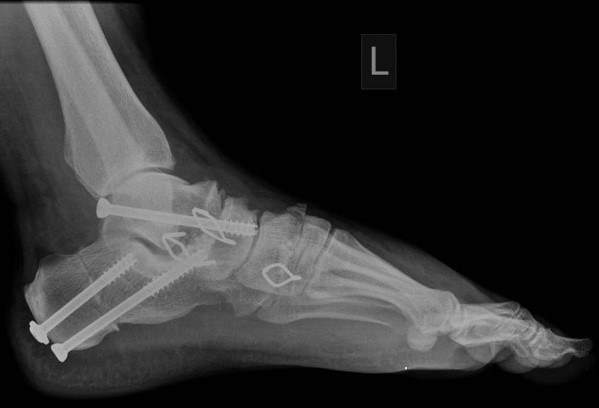

Spektrum operačních výkonů na noze je velmi široké. Cílem většiny z nich je obnovení původních poměrů na noze, a tedy pacientova úleva od bolestí. Jedná se o korekční výkony na kostech, kloubech, o šlachové přenosy nebo rekonstrukce vazů.